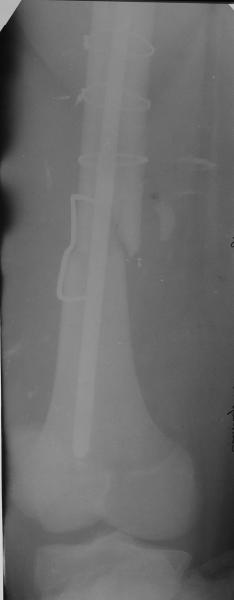

Уважаемые коллеги,пожалуйста, подумайте над следующим ребусом. В нашу клинику поступилпациент из области, 17лет, получивший травму в ДТП 25.08.04, открытый перелом бедра, при поступлении наложено скелетное вытяжение.

30.09.04 на операции выявлен вывих бедра и перелом голени на этой же стороне. Остесинтез бедра все же выполнен, и по заживлении раны пациент переведен к нам. Кроме того у пациента нейропатия седалищного нерва на этой же стороне. В нашей клинике планируется наложение аппарата таз-бедро, для постепенного низведения бедра с последующим открытым вправлением, замена фиксатора на запираемый гвоздь и блокируемый остесинтез голени. Вариант с первичным эндопротезированием мы не рассматривали из-за юного возраста пациента. Вопрос с чего начать? Кроме того, сгибание в коленном суставе в настоящее время (95 градусов) затрудняет остеосинтез голени.Стоит-ли менять гвоздь? Или же спилить торчащий конец во время открытого вправления? Может, попробовать все сделать одномоментно? Заранее спасибо.

Просьба простить за длительное молчание, не было фотоаппарата, чтобы перенести рентгенограммы. Больного прооперировали в прошлый четверг, как и предполагали, голень проблем не доставила(настолько, что даже не ввели дистальные винты по ряду причин: срок после травмы, целая малоберцовая, последующая длительная ходьба без нагрузки, да и гвоздь сел плотно). Изначально планировали после удаления фиксатора антеградно завести стержень и утопить конец, но вопрос был исчерпан, когда выяснилось, что все имеющиеся стержни слишком длинные, пришлось ретроградно забить большеберцовый гвоздь, после рассверливания; серьезные проблемы возникли с устранением ротации. В вертельной области сломали стержень-джойстик(привет установщику эндопротеза), дальнейшие манипуляции проводили пучком спиц и стержнем с кондуктором. Закончили все аппаратом таз-бедро. Решили что возможные огрехи с ротацией устраним после открытого вправления. Снимки прилагаю. Спасибо за участие в обсуждении. Обязуюсь информировать о дальнейших этапах лечения.